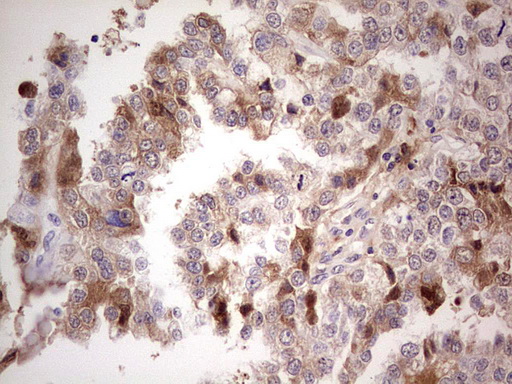

Facts about Complement factor I.

Responsible for cleaving the alpha-chains of C4b and C3b in the presence of the cofactors C4-binding protein and factor H respectively.